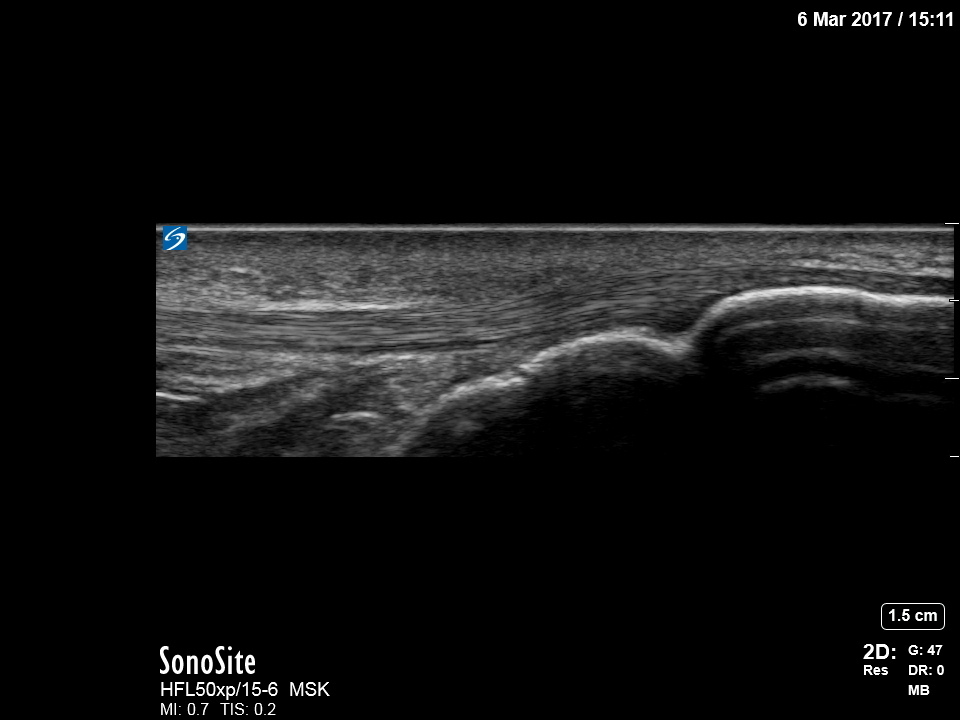

Knee Infrapatellar Normal Image